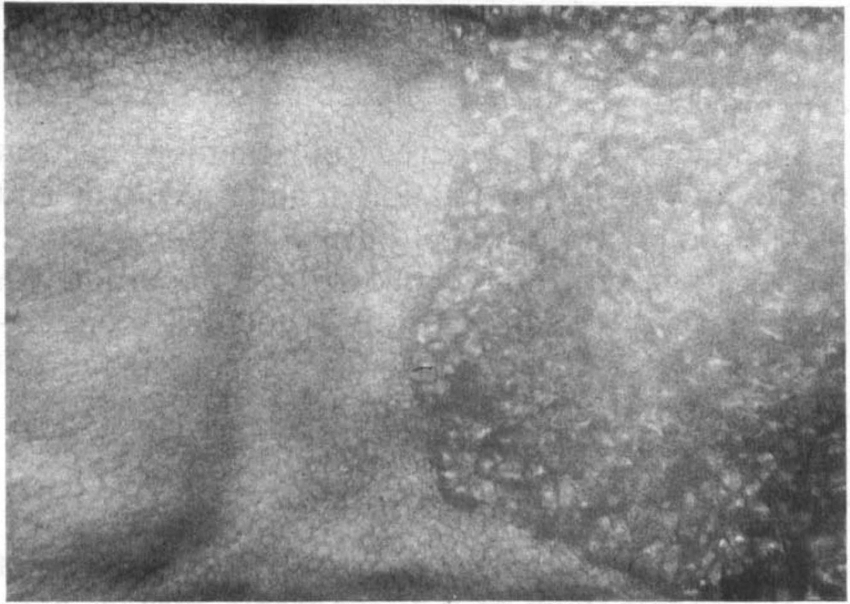

각막내피세포 검사 (specular microscopy)를 이용하여 비정상적인 부분을 촬영시

정상적인 각막내피세포보다 더 크고 어두우며, 한가운데 밝은 흰점이 있는 비정상적인 각막내피세포가 있습니다.

이러한 세포들은 세포의 한가운데에 밝은 점 혹은 세포벽 테두리를 따라서 밝은 선을 가지는 어두운 영역으로 관찰됩니다.

이러한 세포들은 ICE syndrome 에서 특징적인 양상이기 문에, ICE cell 이라고 합니다.

이를 Hammered Silver 라고하는데, ICE cell 을 현미경으로 관찰하였을때 특징적인 모양을

이렇게 표현합니다.